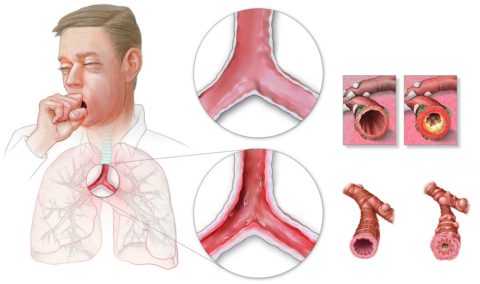

Понятием «бронхит» в медицине обозначают воспалительный процесс, возникающий в слизистой оболочке бронхов.

Бронхит может быть острым, возникшим впервые или повторяющимся не чаще раза в три года. Если же воспаление бронхов возникает чаще, говорят о хронической форме заболевания. Также бронхит бывает обструктивным и необструктивным.

При обструктивной форме возникает спазм бронхов и они перестают проводить воздух в лёгкие (фото). При необструктивной форме такого не происходит.